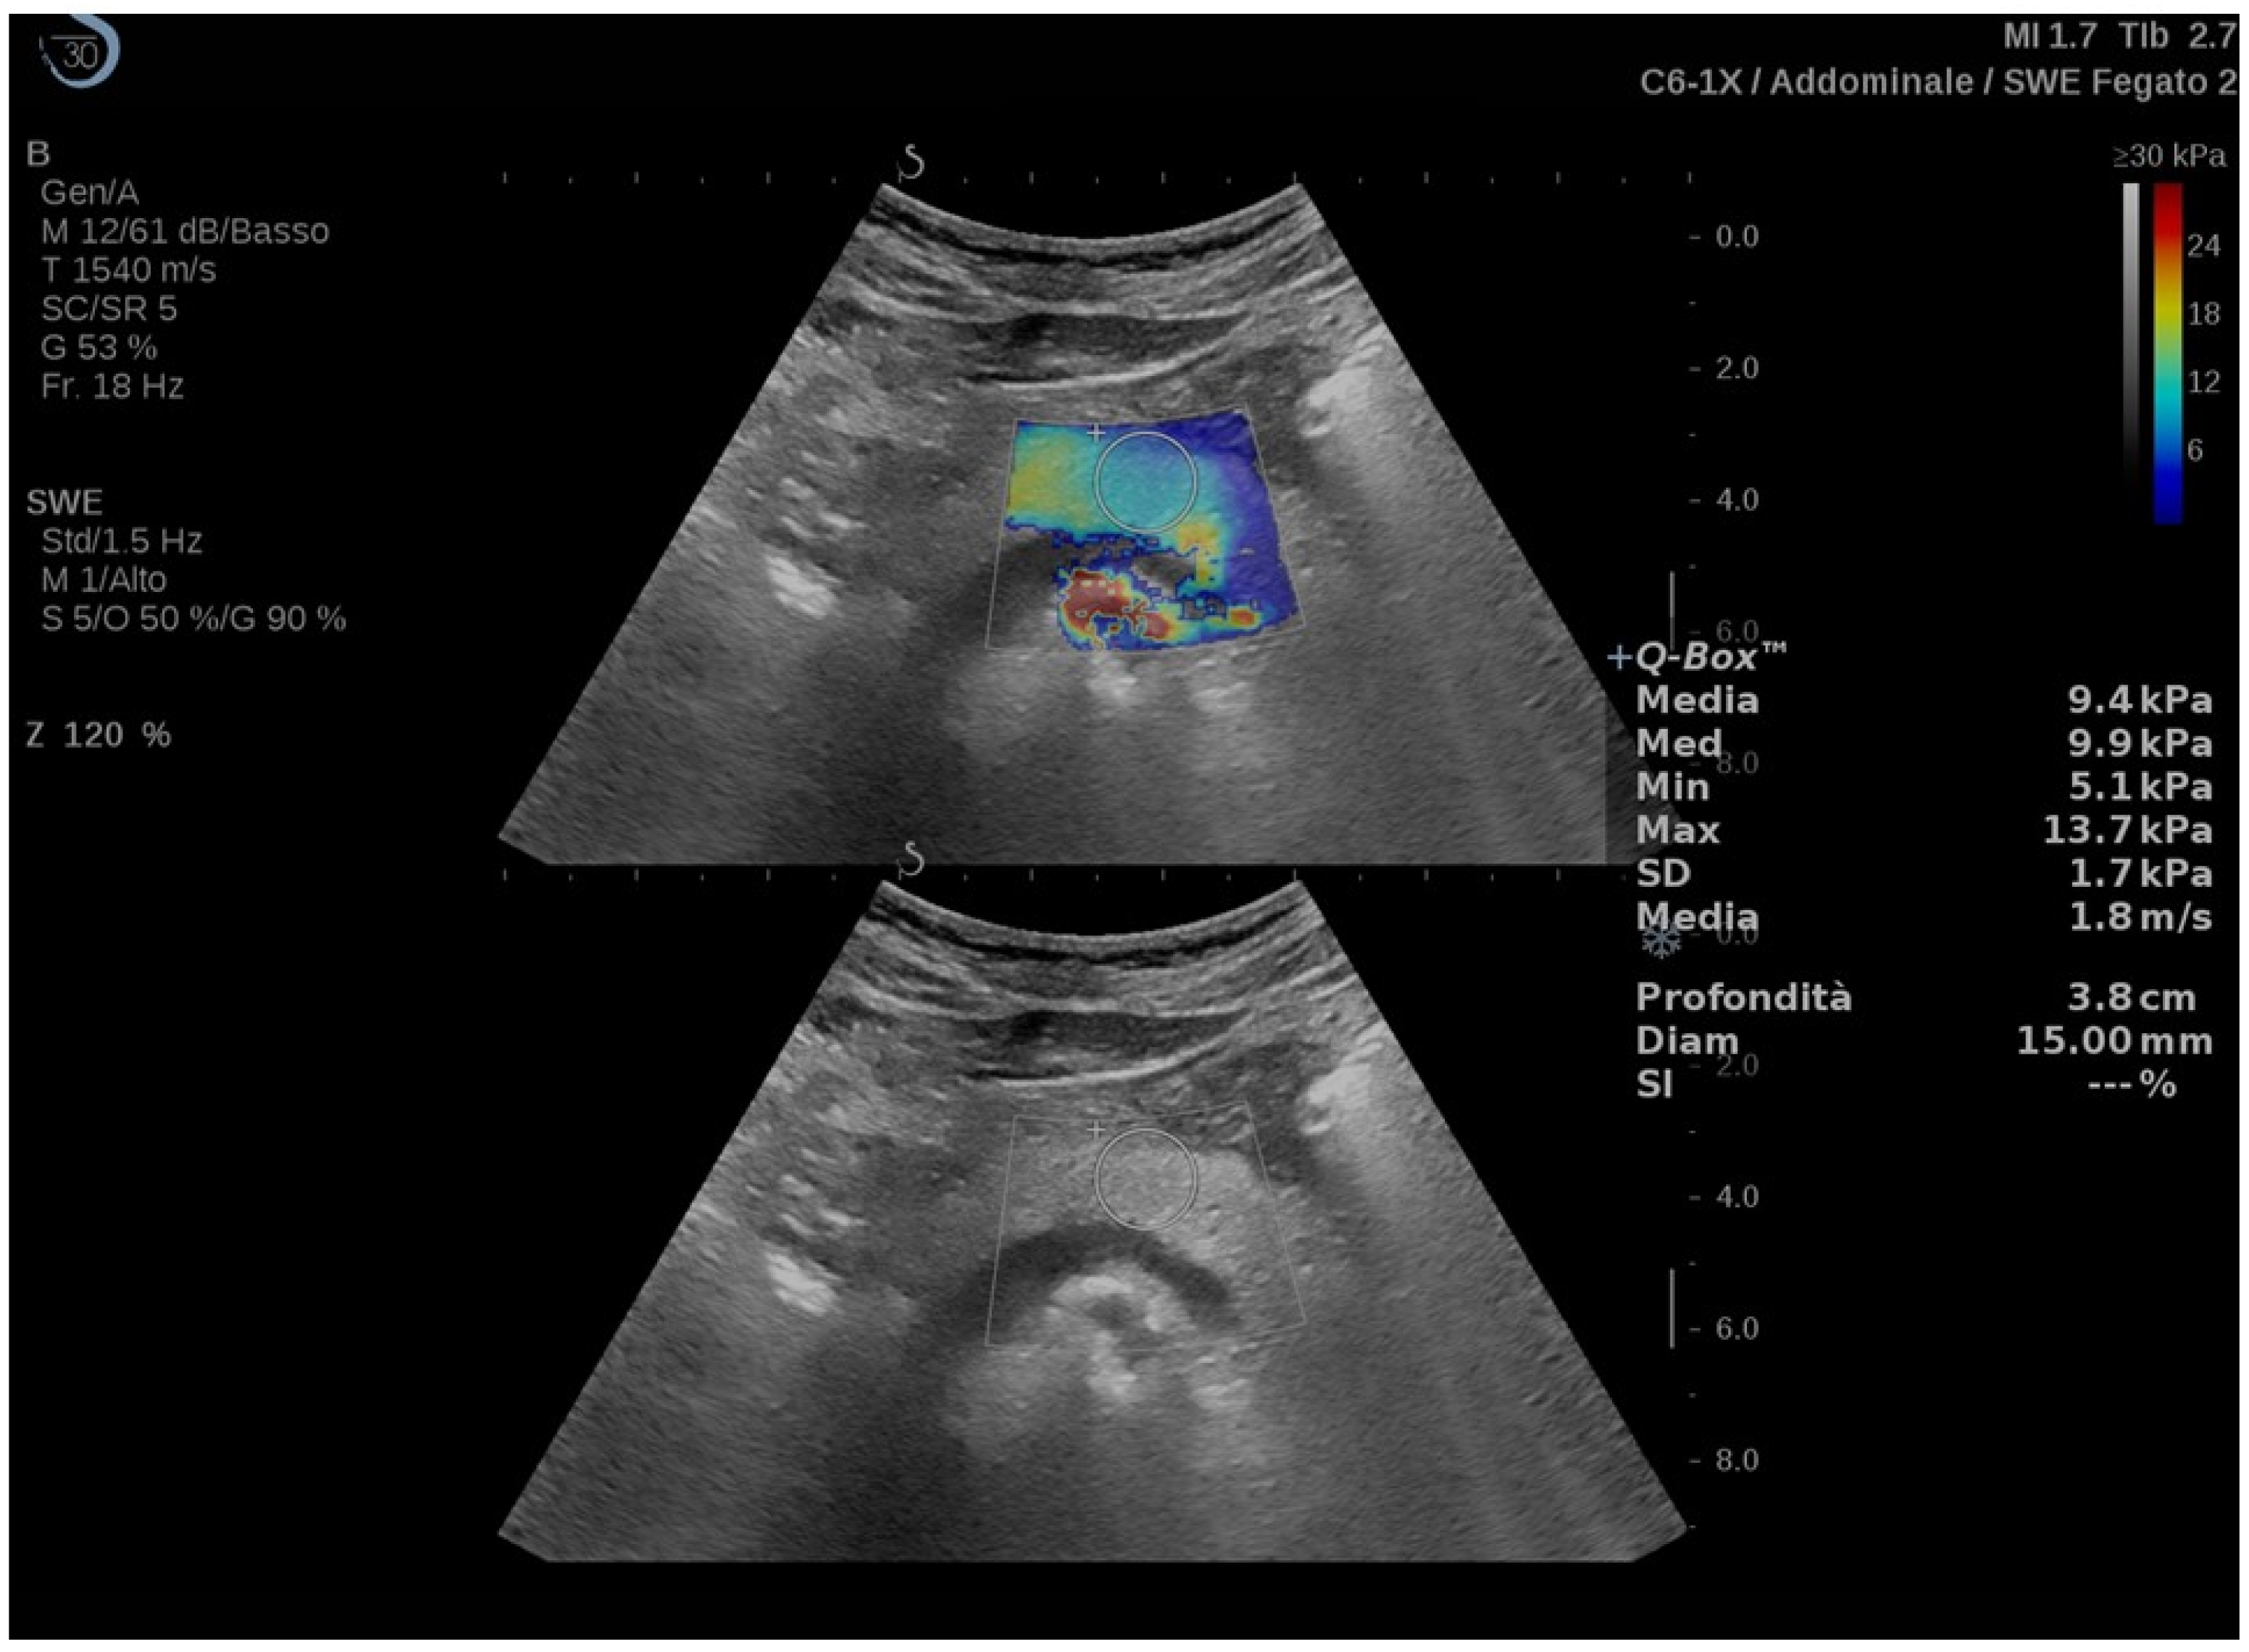

| Chen (2022) [24] | CD | Response to therapy | Prospective (30) | Aixplorer, SuperSonic Imagine | 2D-SWE | 2D-SWE values decreased in responding patients two weeks after starting therapy (15.3 ± 4.7 vs. 12.6 ± 3.3 kPa, p = 0.003). At baseline, 2D-SWE values were higher in non-responders’ group (15.3 ± 4.7 vs. 21.3 ± 8.7 kPa, p = 0.022). | Clinical data and endoscopy |